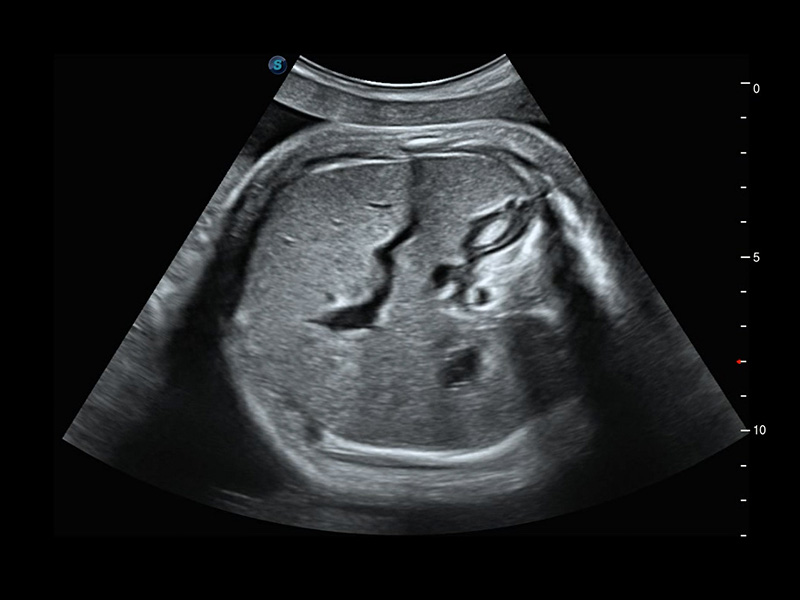

S-Fetus*

S-Fetus è uno strumento di facile utilizzo che consente il rilevamento completamente automatico e preciso dei piani più significativi e delle misurazioni della biometria fetale, utilizzate frequentemente. Con la modalità cine-loop della testa del feto, S-Fetus è in grado di estrarre i piani standard e visualizzare i risultati della misurazione in un secondo, riducendo notevolmente Il numero di battute e i tempi di lavoro necessari. È progettato per trasformare gli esami ecografici ostetrici in un'esperienza molto più comoda, veloce e piacevole.